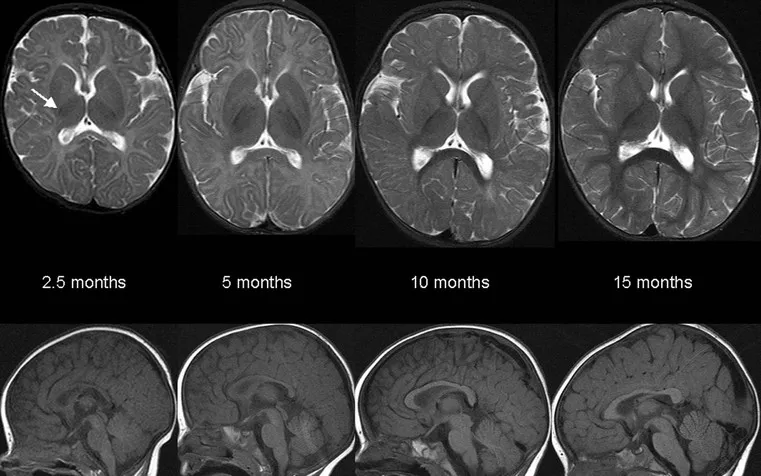

Myelination (Age-dependent): Inferior → superior, post → ant, central → peripheral.

- T1: Myelin ↑. T2: Myelin ↓.

- Birth: Brainstem, PLIC.

- 3-6 mo: ALIC, SCC.

- 6-12 mo: GCC, occipital WM.

- 18-24 mo: Frontal WM (adult by 2 yrs).